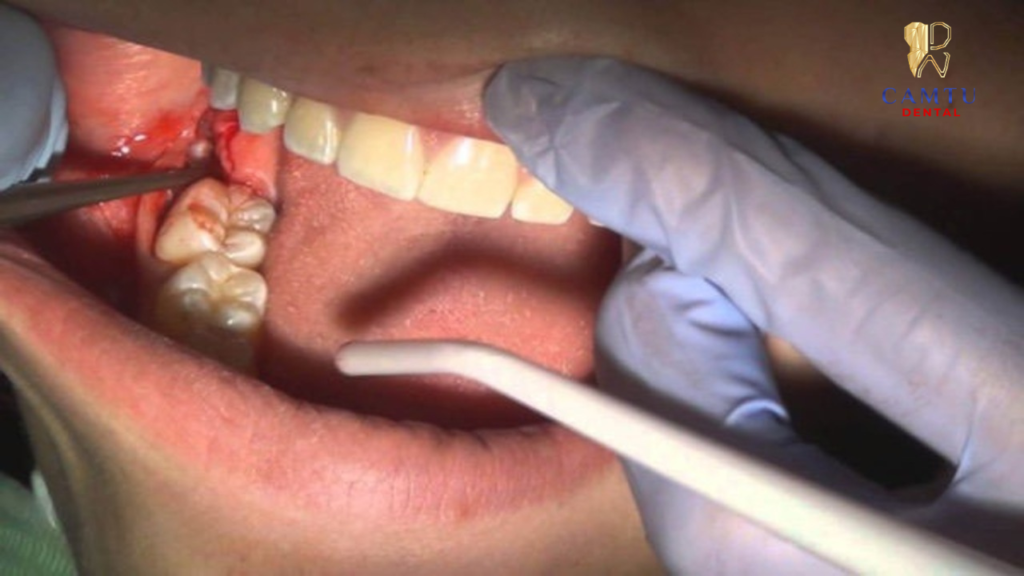

Gây tê và tiến hành nhổ răng

Trước khi thực hiện, bác sĩ tiến hành gây tê cục bộ tại vùng răng cần nhổ để bệnh nhân không cảm thấy đau trong suốt quá trình điều trị. Sau đó, bác sĩ sử dụng các dụng cụ nha khoa chuyên dụng để tách răng khỏi mô nướu và xương hàm một cách nhẹ nhàng, đảm bảo quá trình nhổ răng diễn ra nhanh chóng và an toàn.

Cầm máu và hướng dẫn chăm sóc sau nhổ